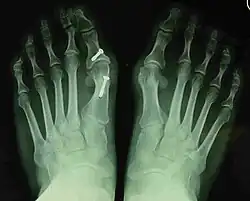

- For recurrence correction after osteotomy procedure (Fig. 8)

Late deformity recurrence can happen after osteotomy (bone-breaking) procedures because osteotomy surgeries do not specifically stabilize first metatarsal bone.

For recurrence correction after fusion procedure (Fig. 9) Metatarsus primus varus deformity and pain recurred 6 months after modified Lapidus procedure and it could also be again corrected by the syndesmosis procedure.